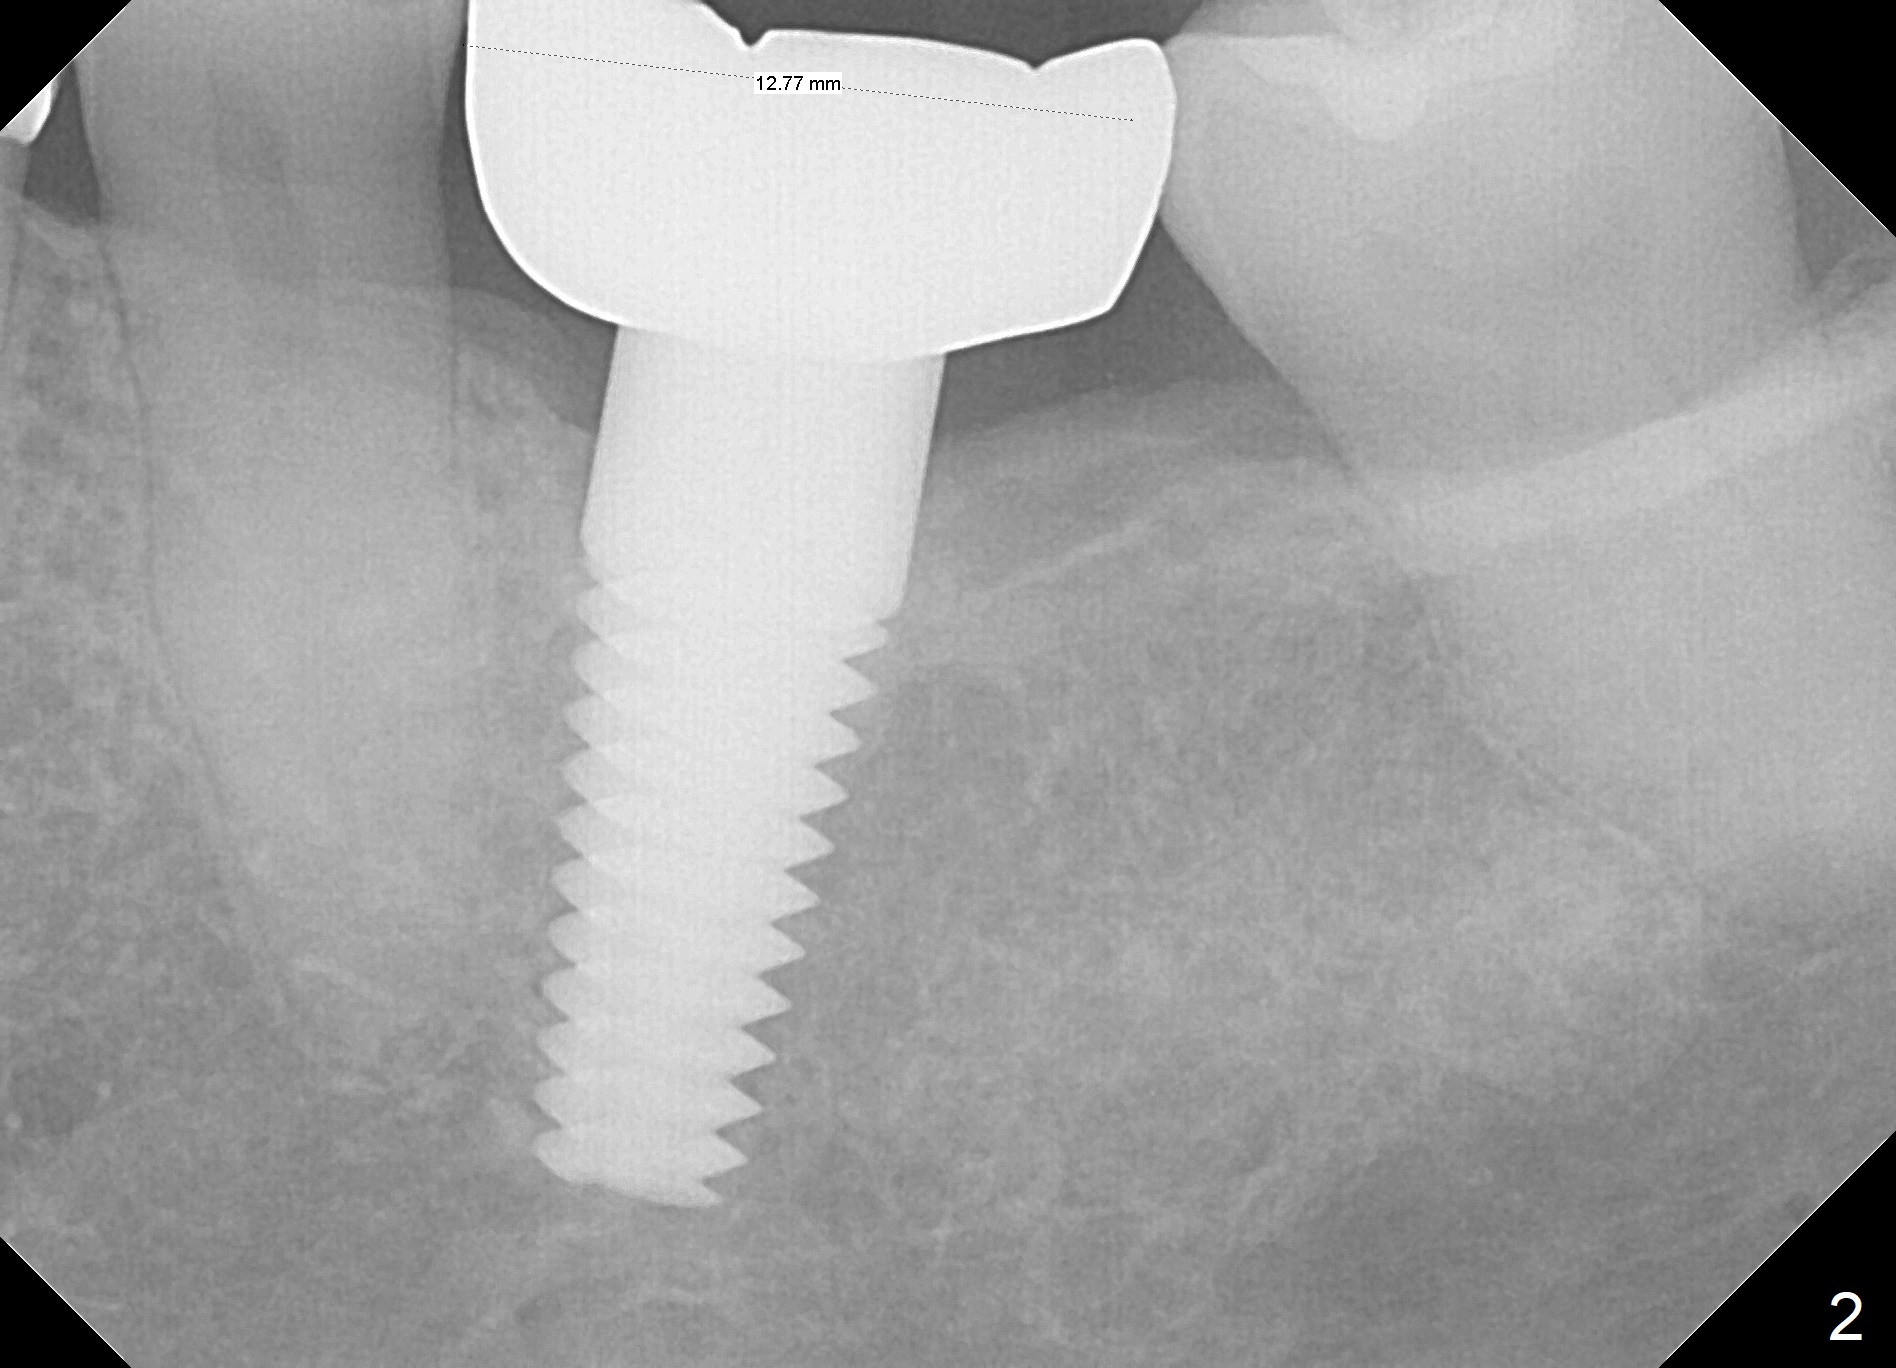

A 53-year-old woman returns for follow-up, requesting implant restoration at the sites of #30 and 31. The edentulous space is ~14 mm mesiodistally (Fig.1), whereas a 6x17 mm implant was placed at #19 with ~13 mm space (Fig.2). If the ridge at the LR molar region is wide enough buccolingually (3.5-5 mm Implant Positioners), place one implant (Fig.3, 4 mm Implant Spacer). Otherwise, two of them will be placed (Fig.4).